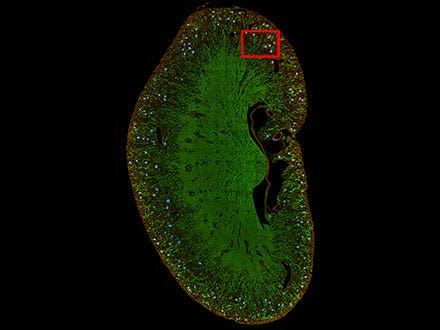

4) 組織標本のセグメンテーション

TruAIは、細胞だけでなく組織標本のセグメンテーションにも活用できます。例えば腎臓の糸球体のように、目視などのマニュアルな方法以外では判別が困難なものも、ニューラルネットワークを学習させればセグメンテーションが可能です。また、組織全体がイメージングされた広範囲の貼り合わせ画像にも活用できます。

図8: マウスの腎臓切片画像から糸球体の位置をTruAIで推論した結果(青)

図9: TruAIが糸球体の特徴を捉えて検出